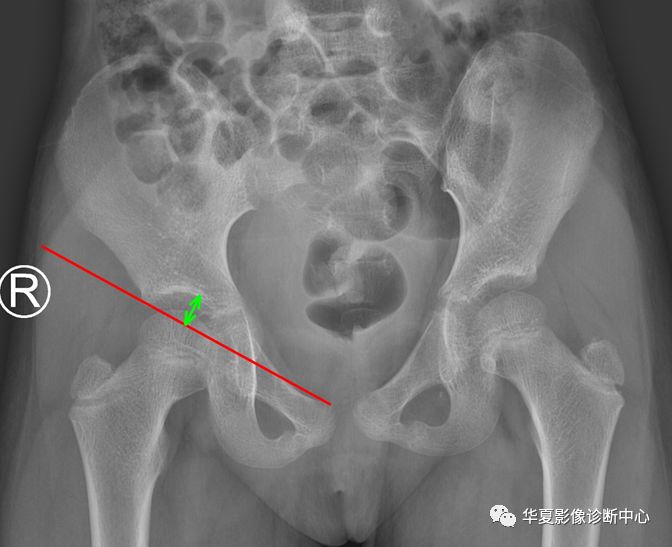

3、Shenton线(耻颈线):髋关节正位片上,闭孔上缘与股骨颈内下缘连线。 医学百科网 | YxBaike.Com

正常应为平滑曲线,若不连续提示髋关节脱位或者股骨颈错位骨折。